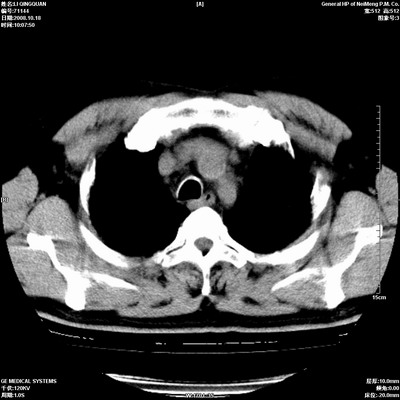

以下是引用duguo在2008-10-19 13:59:00的发言:[br]左肺上叶支气管狭窄,首先考虑中心型肺癌伴阻塞性肺炎\\肺不张.

以下是引用ybing在2008-10-19 12:58:00的发言:[br]左肺上叶阻塞性炎症-建议支气管镜进一步检查除外中央型肺癌

以下是引用随光逐影在2008-10-19 14:31:00的发言:[br]考虑左肺中央型肺癌并左肺上叶阻塞性肺炎,肺不张。